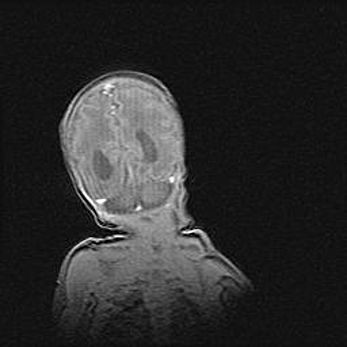

Лейкомаляция с кистозно-глиозной дегенерацией головного мозга.

Возраст: 2 месяца 25 дней

Вес: 6400 г

Окружность головы: 40 см

Срок гестации: 41 неделя

Лейкомаляцию относят к ишемически-гипоксическим повреждениям головного мозга, диагностируемым у новорожденных. При лейкомаляции в головном мозге обнаруживают очаги некроза, возникшие после тяжелой гипоксии и нарушения кровотока. В процессе морфогенеза очаги проходят три стадии: 1) развития некроза, 2) резорбции и 3) формирования глиозного рубца или кисты. Перивентрикулярная лейкомаляция (ПЛ) встречается примерно в 12% случаев среди новорожденных, обычно – у недоношенных детей, причем, частота ее зависит от массы, с которой младенец появился на свет. Наибольшее число малышей страдает лейкомаляцией, если масса при рождении 1500-2500 г.